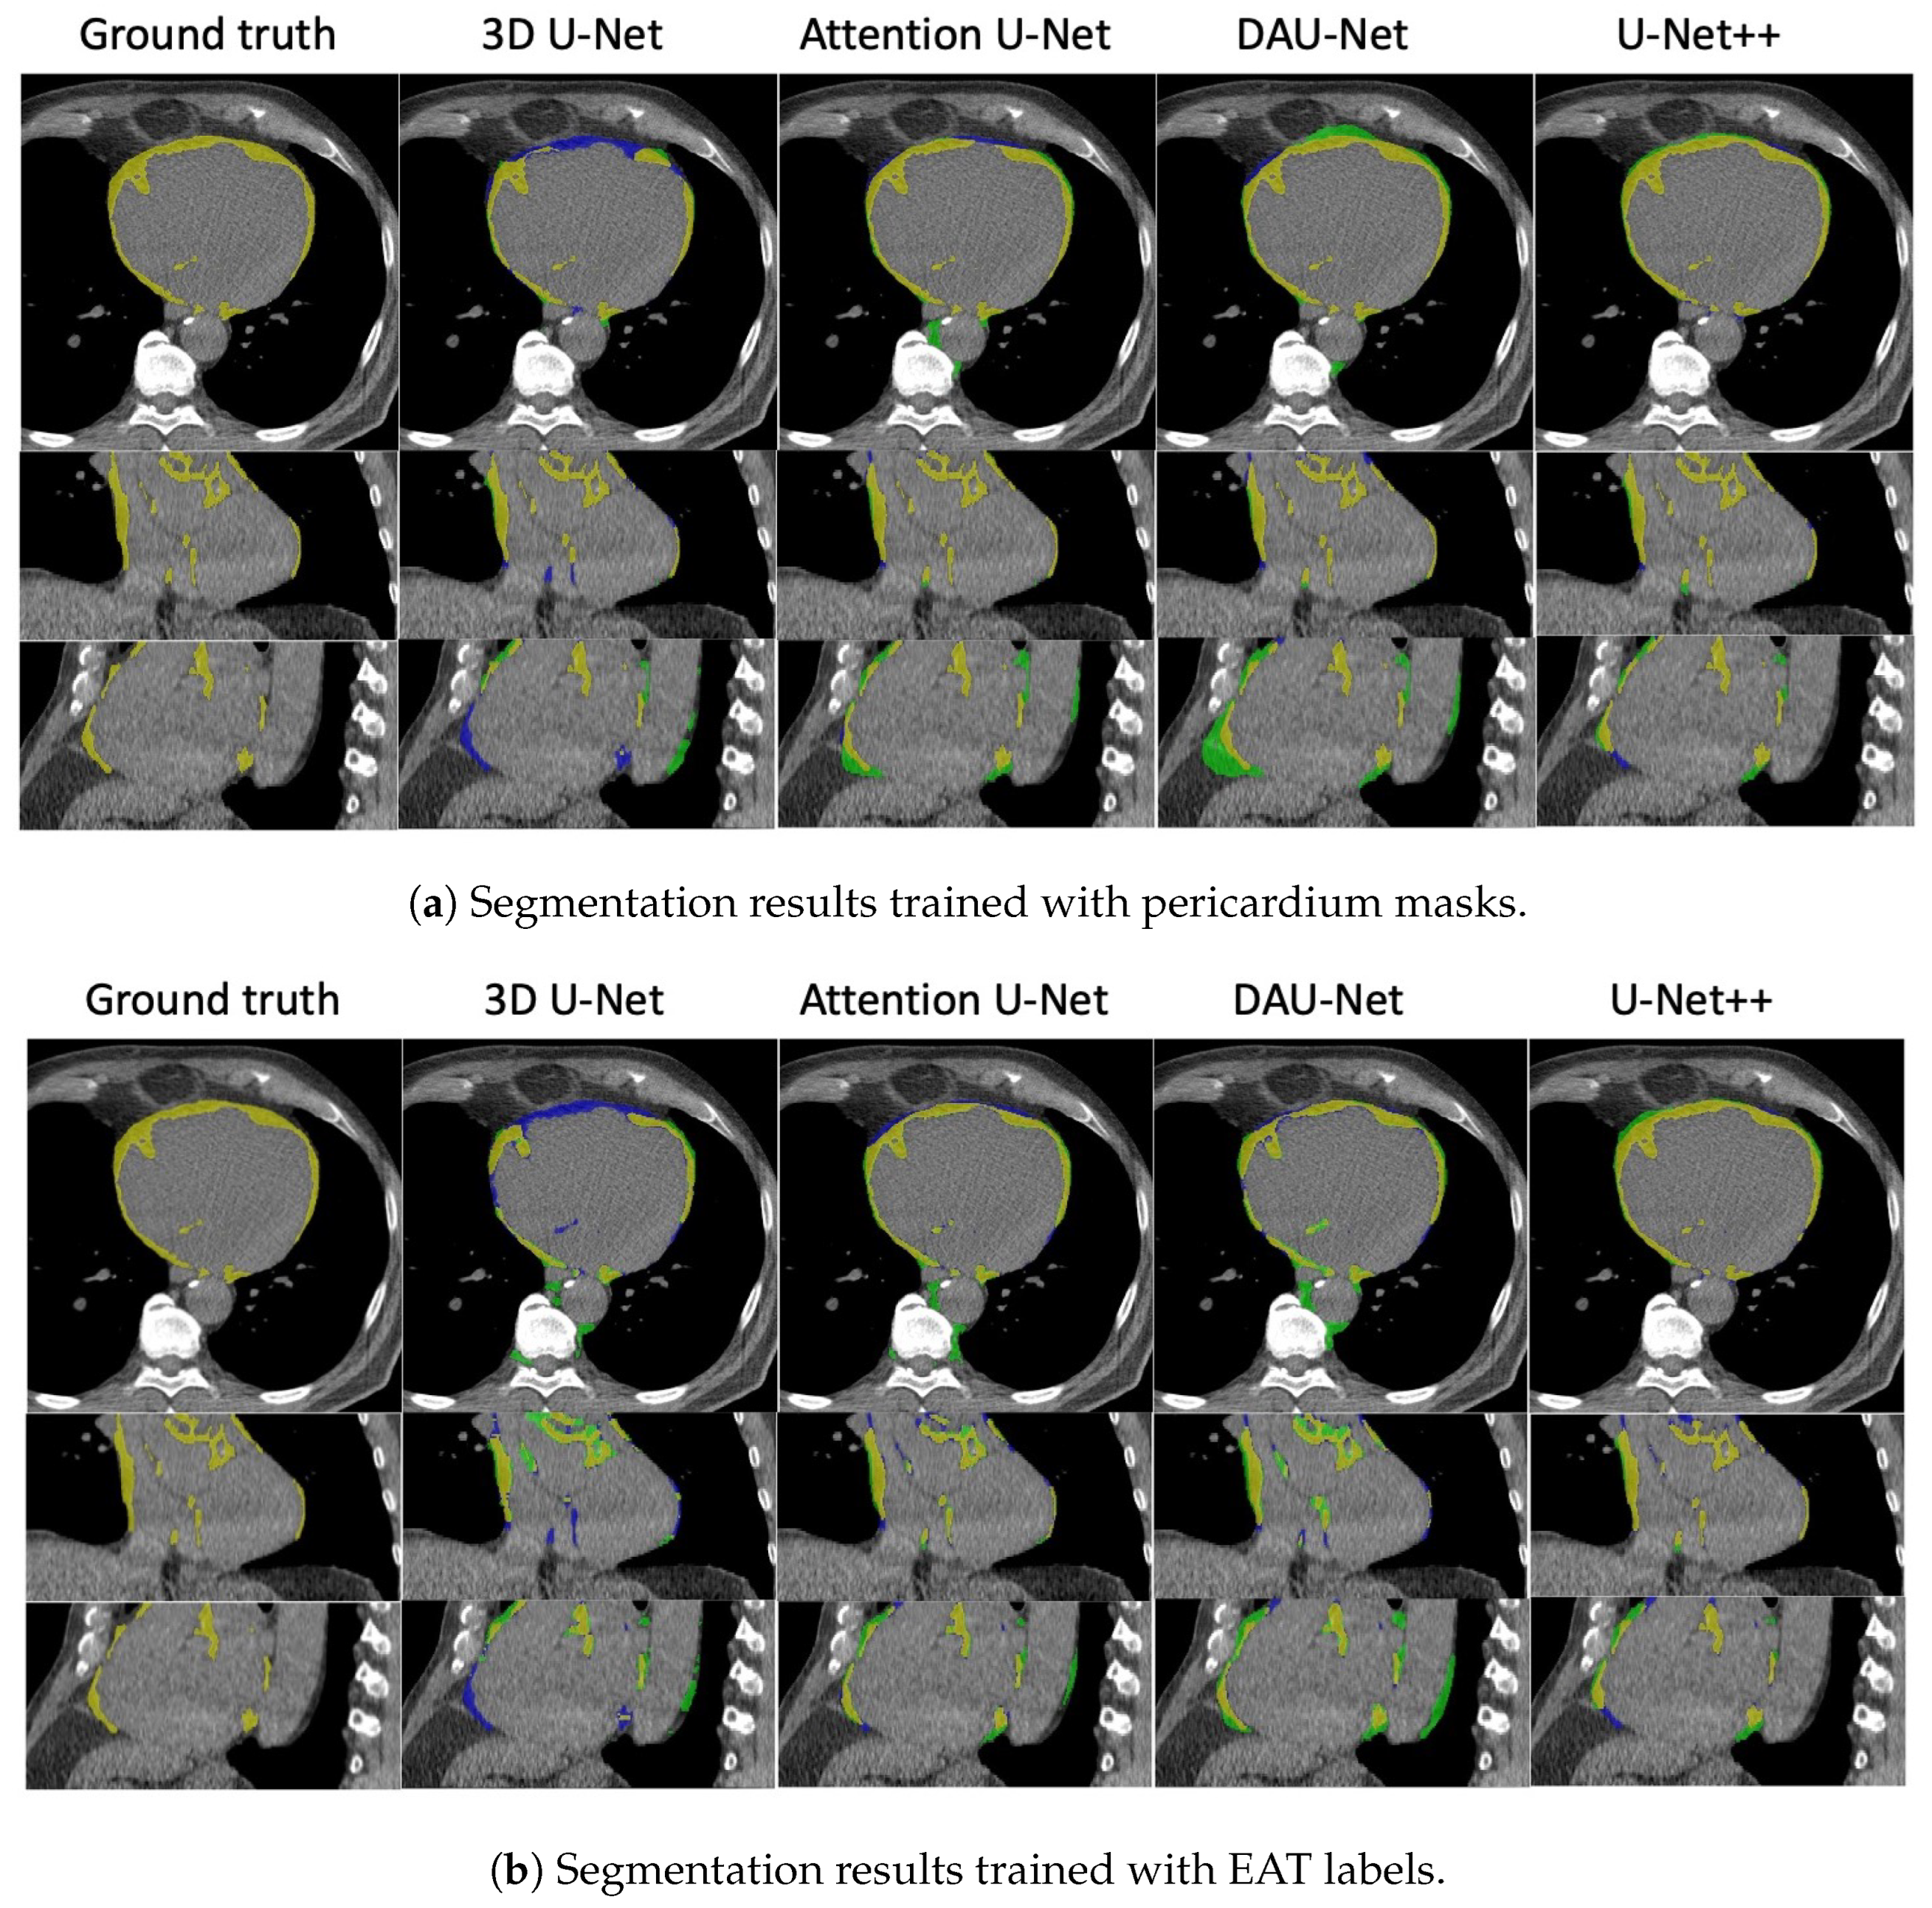

| Model | Label Type | DSC (%) | mIoU (%) | Sensitivity (%) | Specificity (%) | Correlation |

|---|---|---|---|---|---|---|

| 3D U-Net | Pericardium | 0.7588 | ||||

| EAT | 0.5648 | |||||

| 3D attention U-Net | Pericardium | 0.2085 | ||||

| EAT | 0.3883 | |||||

| DAU-Net | Pericardium | 0.8448 | ||||

| EAT | 0.8596 | |||||

| U-Net++ | Pericardium | 0.9123 | ||||

| EAT | 0.7303 |

| 3D U-Net | Pericardium | 0.6661 | ||||

| EAT | 0.6293 | |||||

| 3D attention U-Net | Pericardium | 0.5120 | ||||

| EAT | 0.1386 | |||||

| DAU-Net | Pericardium | 0.8445 | ||||

| EAT | 0.8047 | |||||

| U-Net++ | Pericardium | 0.9606 | ||||

| EAT | 0.9405 |